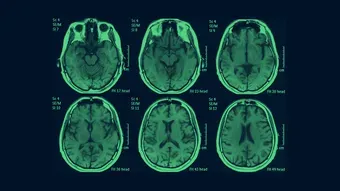

Syndrome du bébé secoué, un scandale français